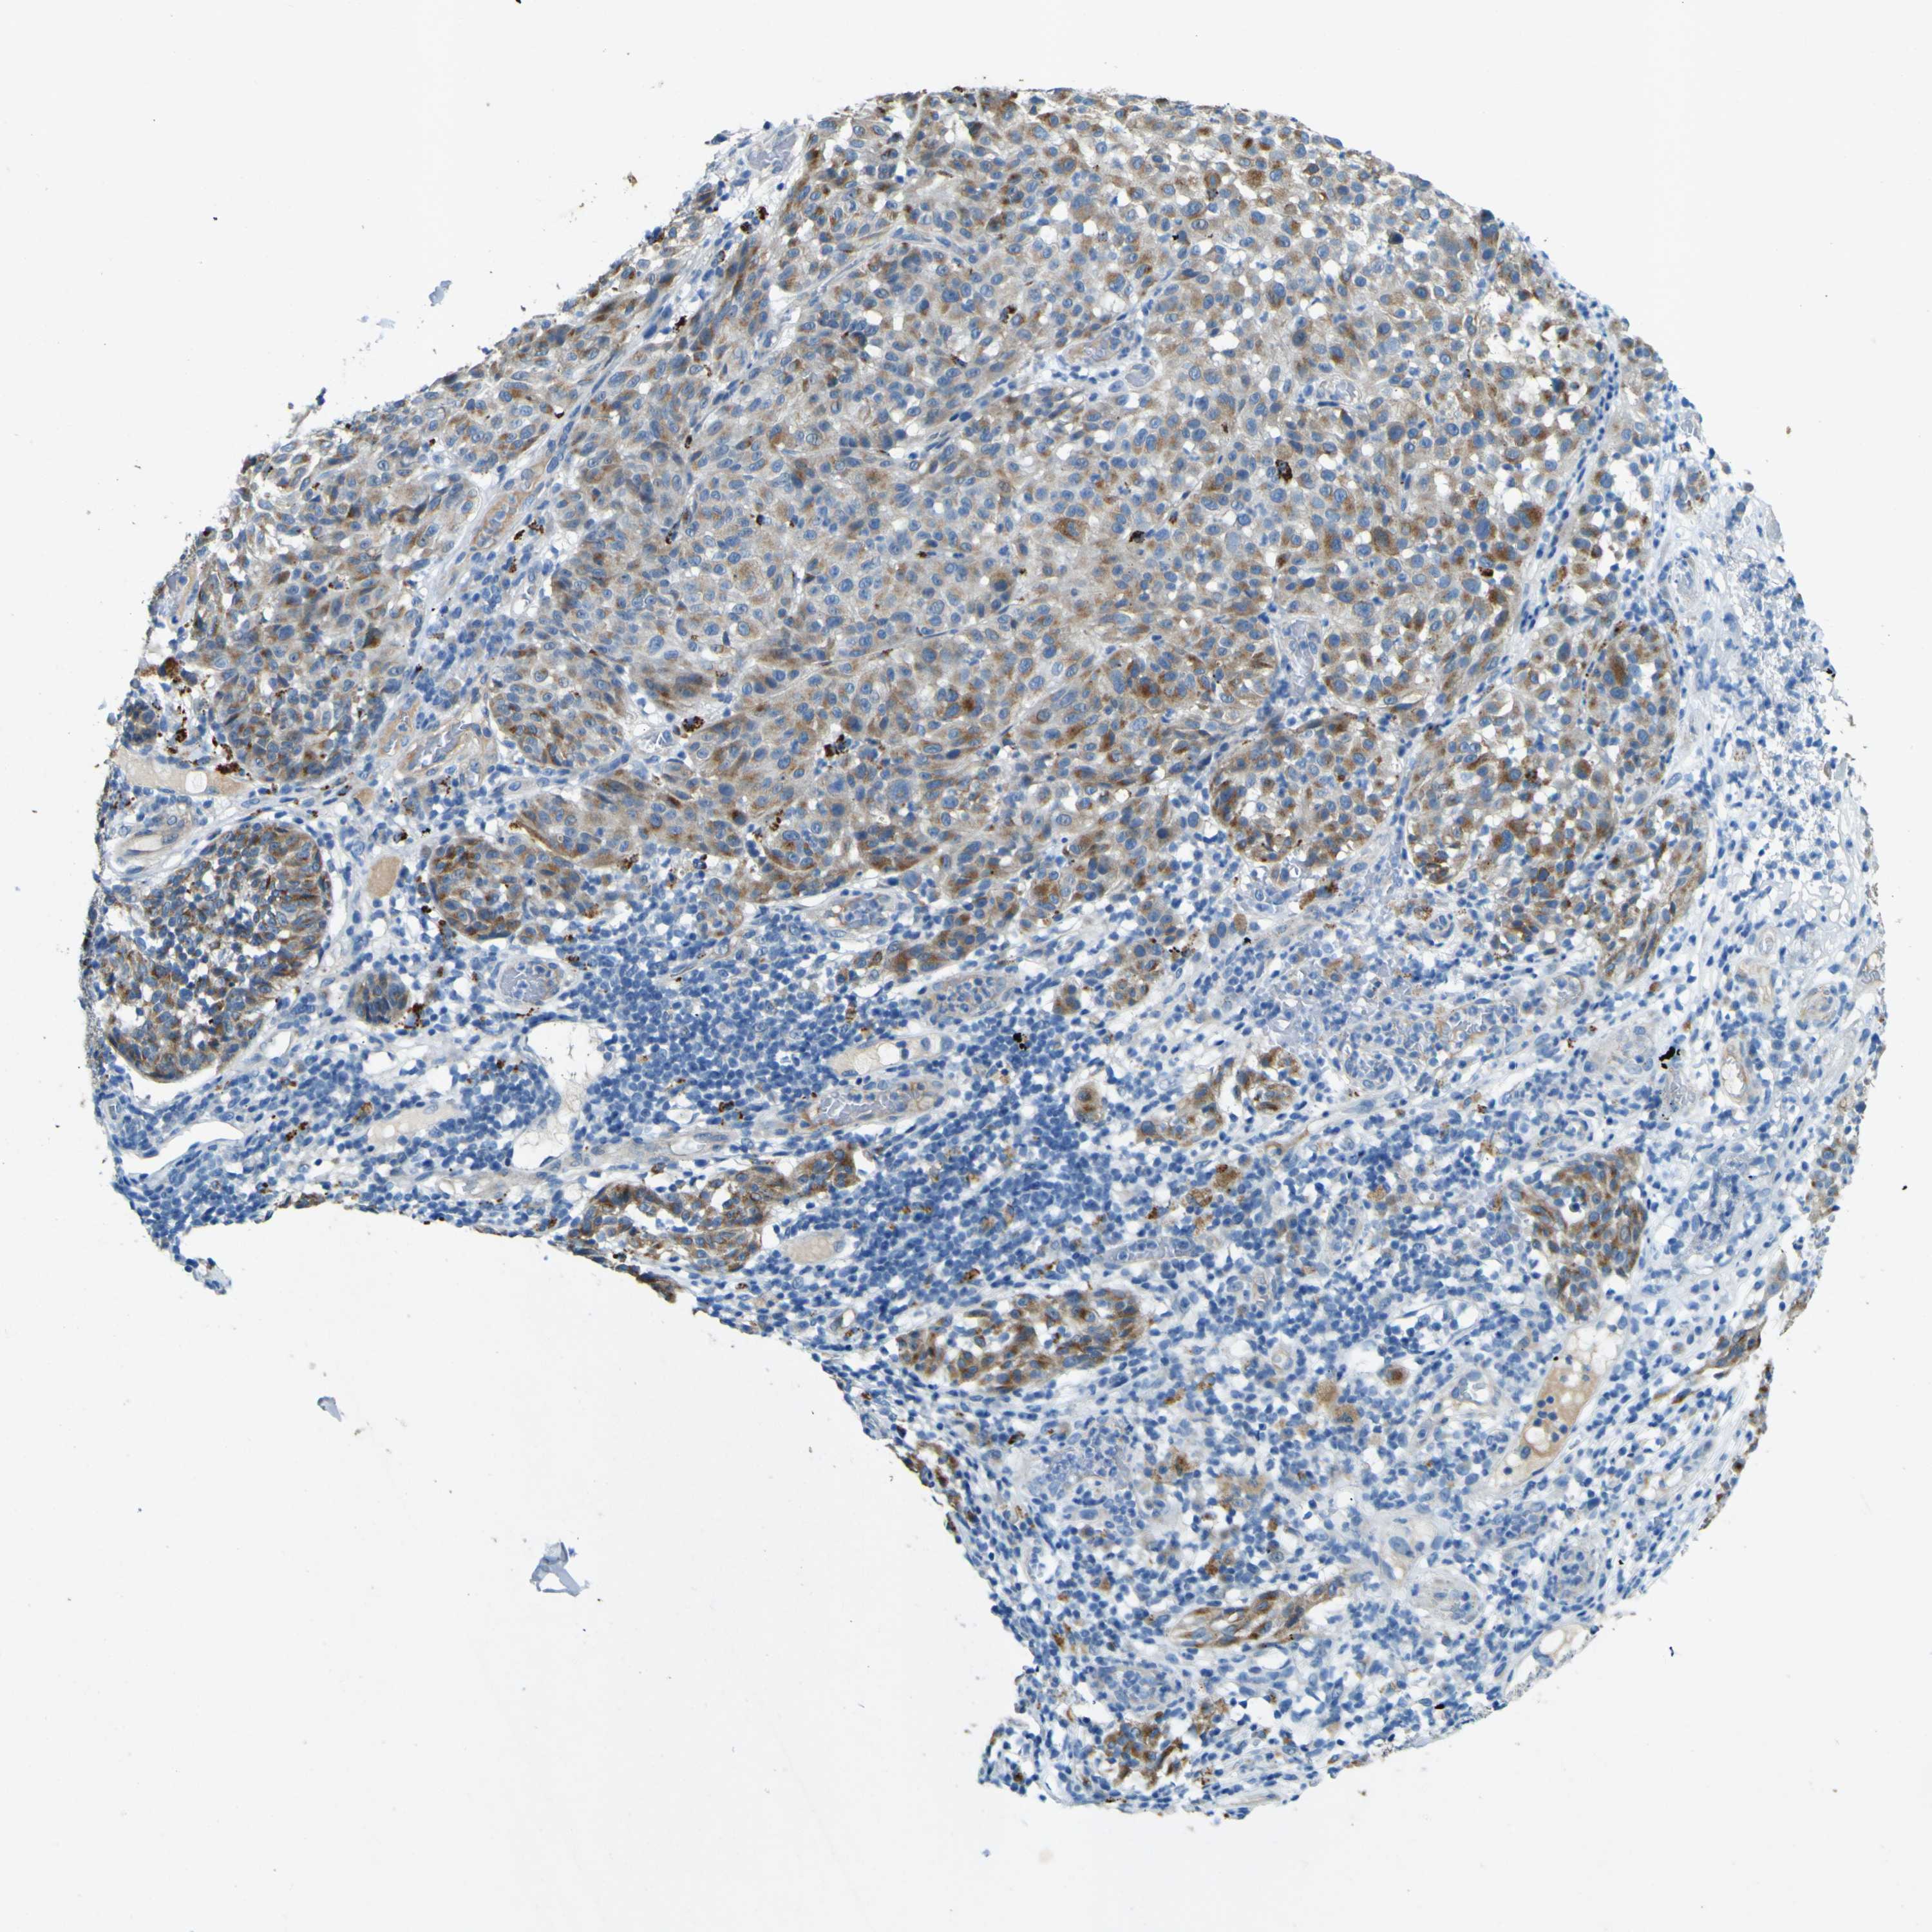

MELANOMA - Protein expressioni

A mouse-over function shows sample information and annotation data. Click on an image to view it in a full screen mode. Samples can be filtered based on level of antibody staining by selecting one or several of the following categories: high, medium, low and not detected. The assay and annotation is described here.

Note that samples used for immunohistochemistry by the Human Protein Atlas do not correspond to samples in the TCGA dataset.

Antibody stainingi

Antibody staining in the annotated cell types in the current human tissue is reported as not detected, low, medium, or high, based on conventional immunohistochemistry profiling in selected tissues. This score is based on the combination of the staining intensity and fraction of stained cells.

Each image is clickable and will lead to virtual microscopy that enables deeper exploration of all samples and also displays staining intensity scores, fraction scores and subcellular localization as well as patient and tissue information for each sample.

Antibody HPA011380

Staining

High

Medium

Low

Not detected

Intensity

Strong

Moderate

Weak

Negative

Quantity

>75%

75%-25%

<25%

None

Location

Nuclear

Cytoplasmic/membranous

Cytoplasmic/membranous,nuclear

Malignant melanoma, NOS

Malignant melanoma, Metastatic site